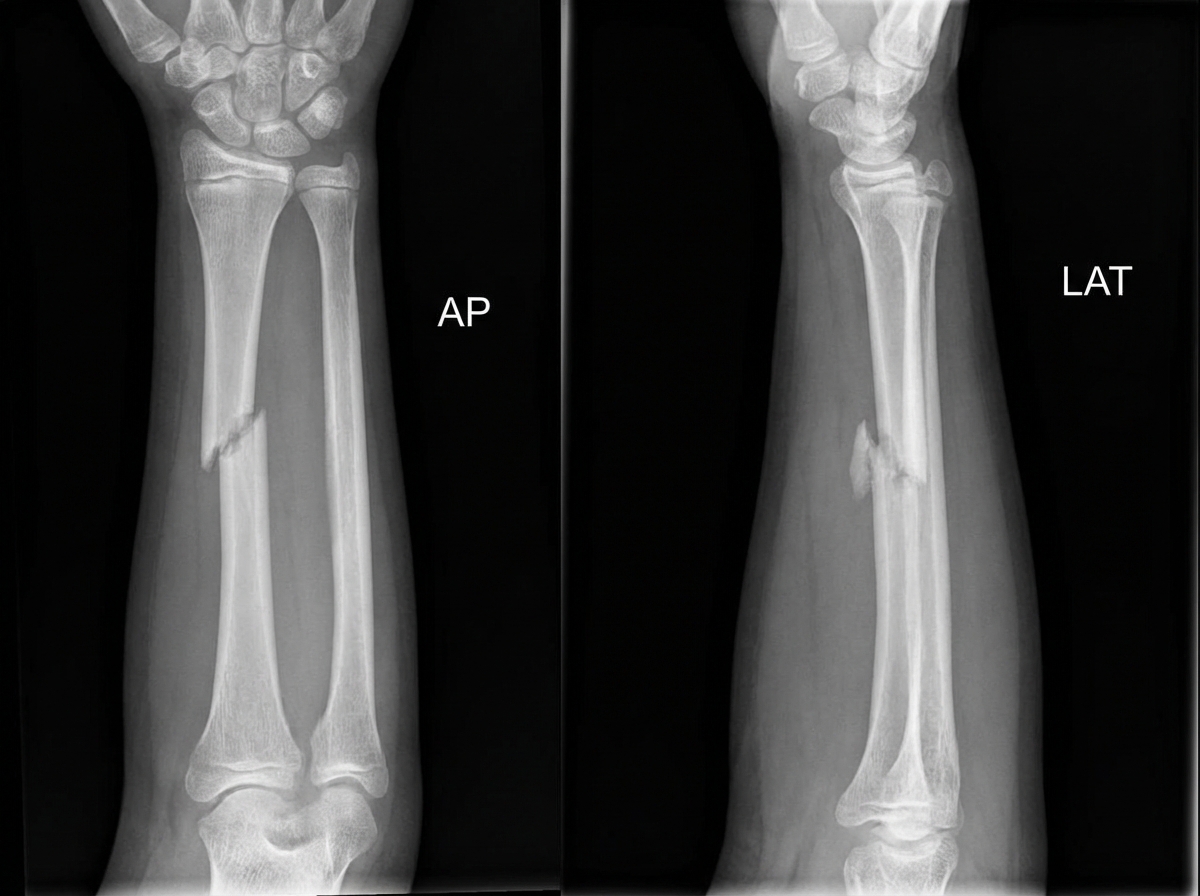

A 13-year-old male presents with forearm pain and deformity after a fall onto his palm. Examination reveals an obvious angulation at the mid-forearm, with intact finger movement, circulation, and sensation. X-rays of the forearm are obtained. What is the most likely diagnosis?

Explanation: ***Galeazzi's fracture*** - **Fall onto outstretched hand (FOOSH)** mechanism with mid-forearm angulation suggests **radius shaft fracture** at the middle/distal third with **distal radioulnar joint (DRUJ) disruption**. - Common in **adolescents** and presents with obvious **forearm deformity** and preserved neurovascular function, as described in this case. *Night-stick fracture* - Results from **direct blow** to the forearm, typically causing an **isolated ulnar shaft fracture** without radial involvement. - Does not typically cause the **obvious angulation** seen in this case, as the radius remains intact to maintain some structural support. *Monteggia's fracture* - Involves **proximal ulnar fracture** with **radial head dislocation**, not mid-forearm deformity. - Typically occurs from **fall on extended arm** but presents with **elbow deformity** and limited **elbow flexion**, not mid-forearm angulation. *Colles' fracture* - **Distal radius fracture** near the **wrist joint** causing characteristic **dinner fork deformity** at the wrist. - Occurs from FOOSH mechanism but affects the **distal radius metaphysis**, not the mid-forearm shaft as described.